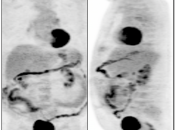

Bladder Hernia

While the CT appearance of this finding should never be missed, its striking PET appearance has led more than one PET/CT reader astray.

Usually, the supero-lateral margin of the bladder will be seen partially entering the inguinal canal. Occasionally, a significant segment of the bladder may extend deep into the hernia defect.

Caveat: Never be duped by an unusual focus of intense metabolic activity anywhere in the body. Always rule out every possible non-neoplastic explanation before raising the specter of cancer.